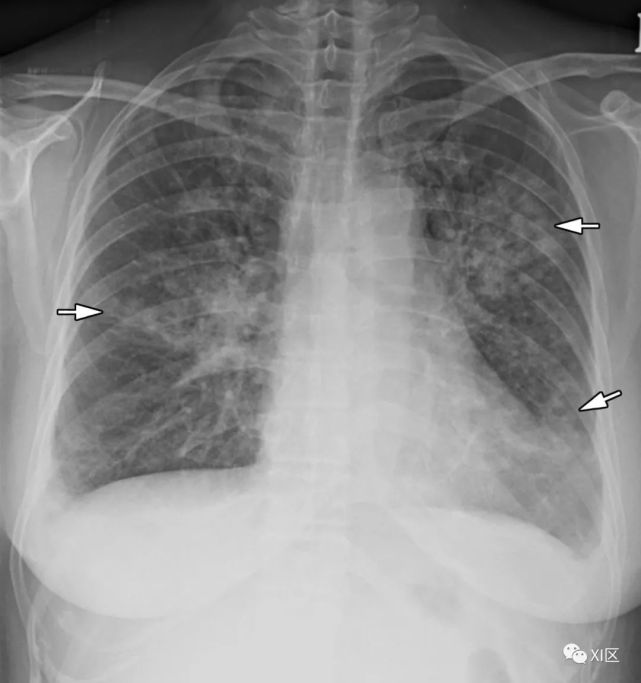

图8 20岁男子因腺病毒感染引起肺炎,伴有发热、咳嗽和呼吸困难。

(上) 最初的胸片显示左中下肺和右下肺区有不明确的斑片状实变和GGO(箭头)。同一天在叶间支气管水平(中)和肺下静脉水平(下)上获得的轴位胸部CT图像(厚度为5mm)显示不明确的斑片状GGO(箭头)和大叶实变(箭)。

Koo H J , Lim S , Choe J , et al. Radiographic and CT Features of Viral Pneumonia[J]. Radiographics, 2018, 38(3):719-739.